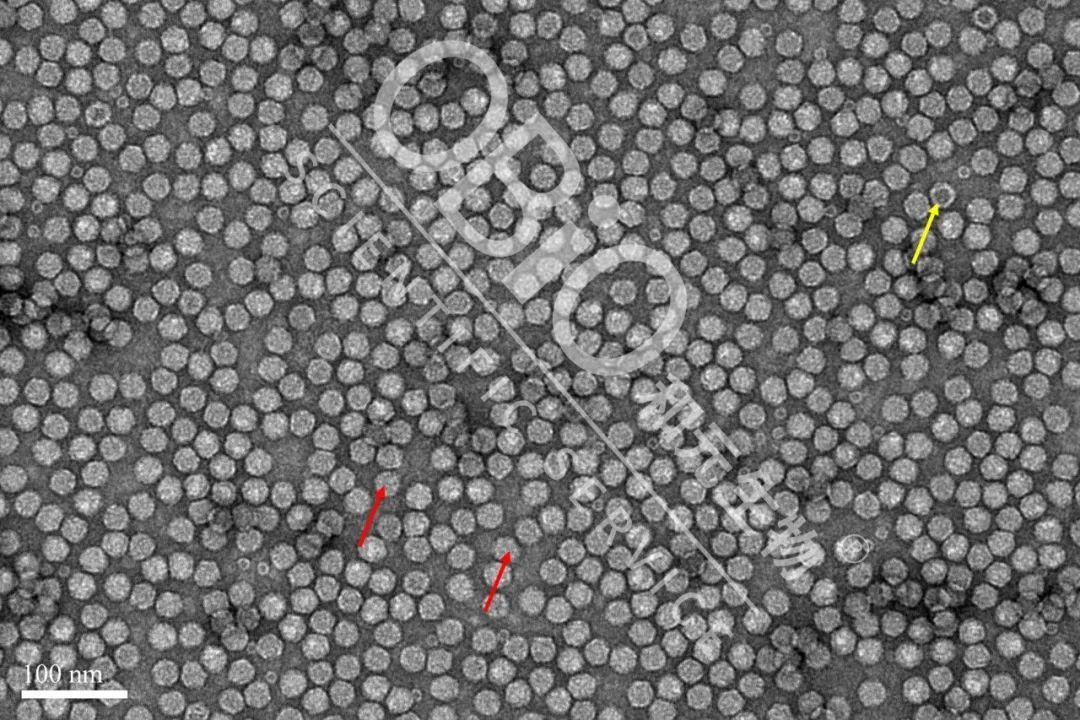

图3 k8凯发(中国)天生赢家·一触即发 rAAV载体生产空壳率

电镜结果:包装DNA基因组的病毒颗粒为实心颗粒(红色箭头);空病毒颗粒中间存在空洞(黄色箭头)